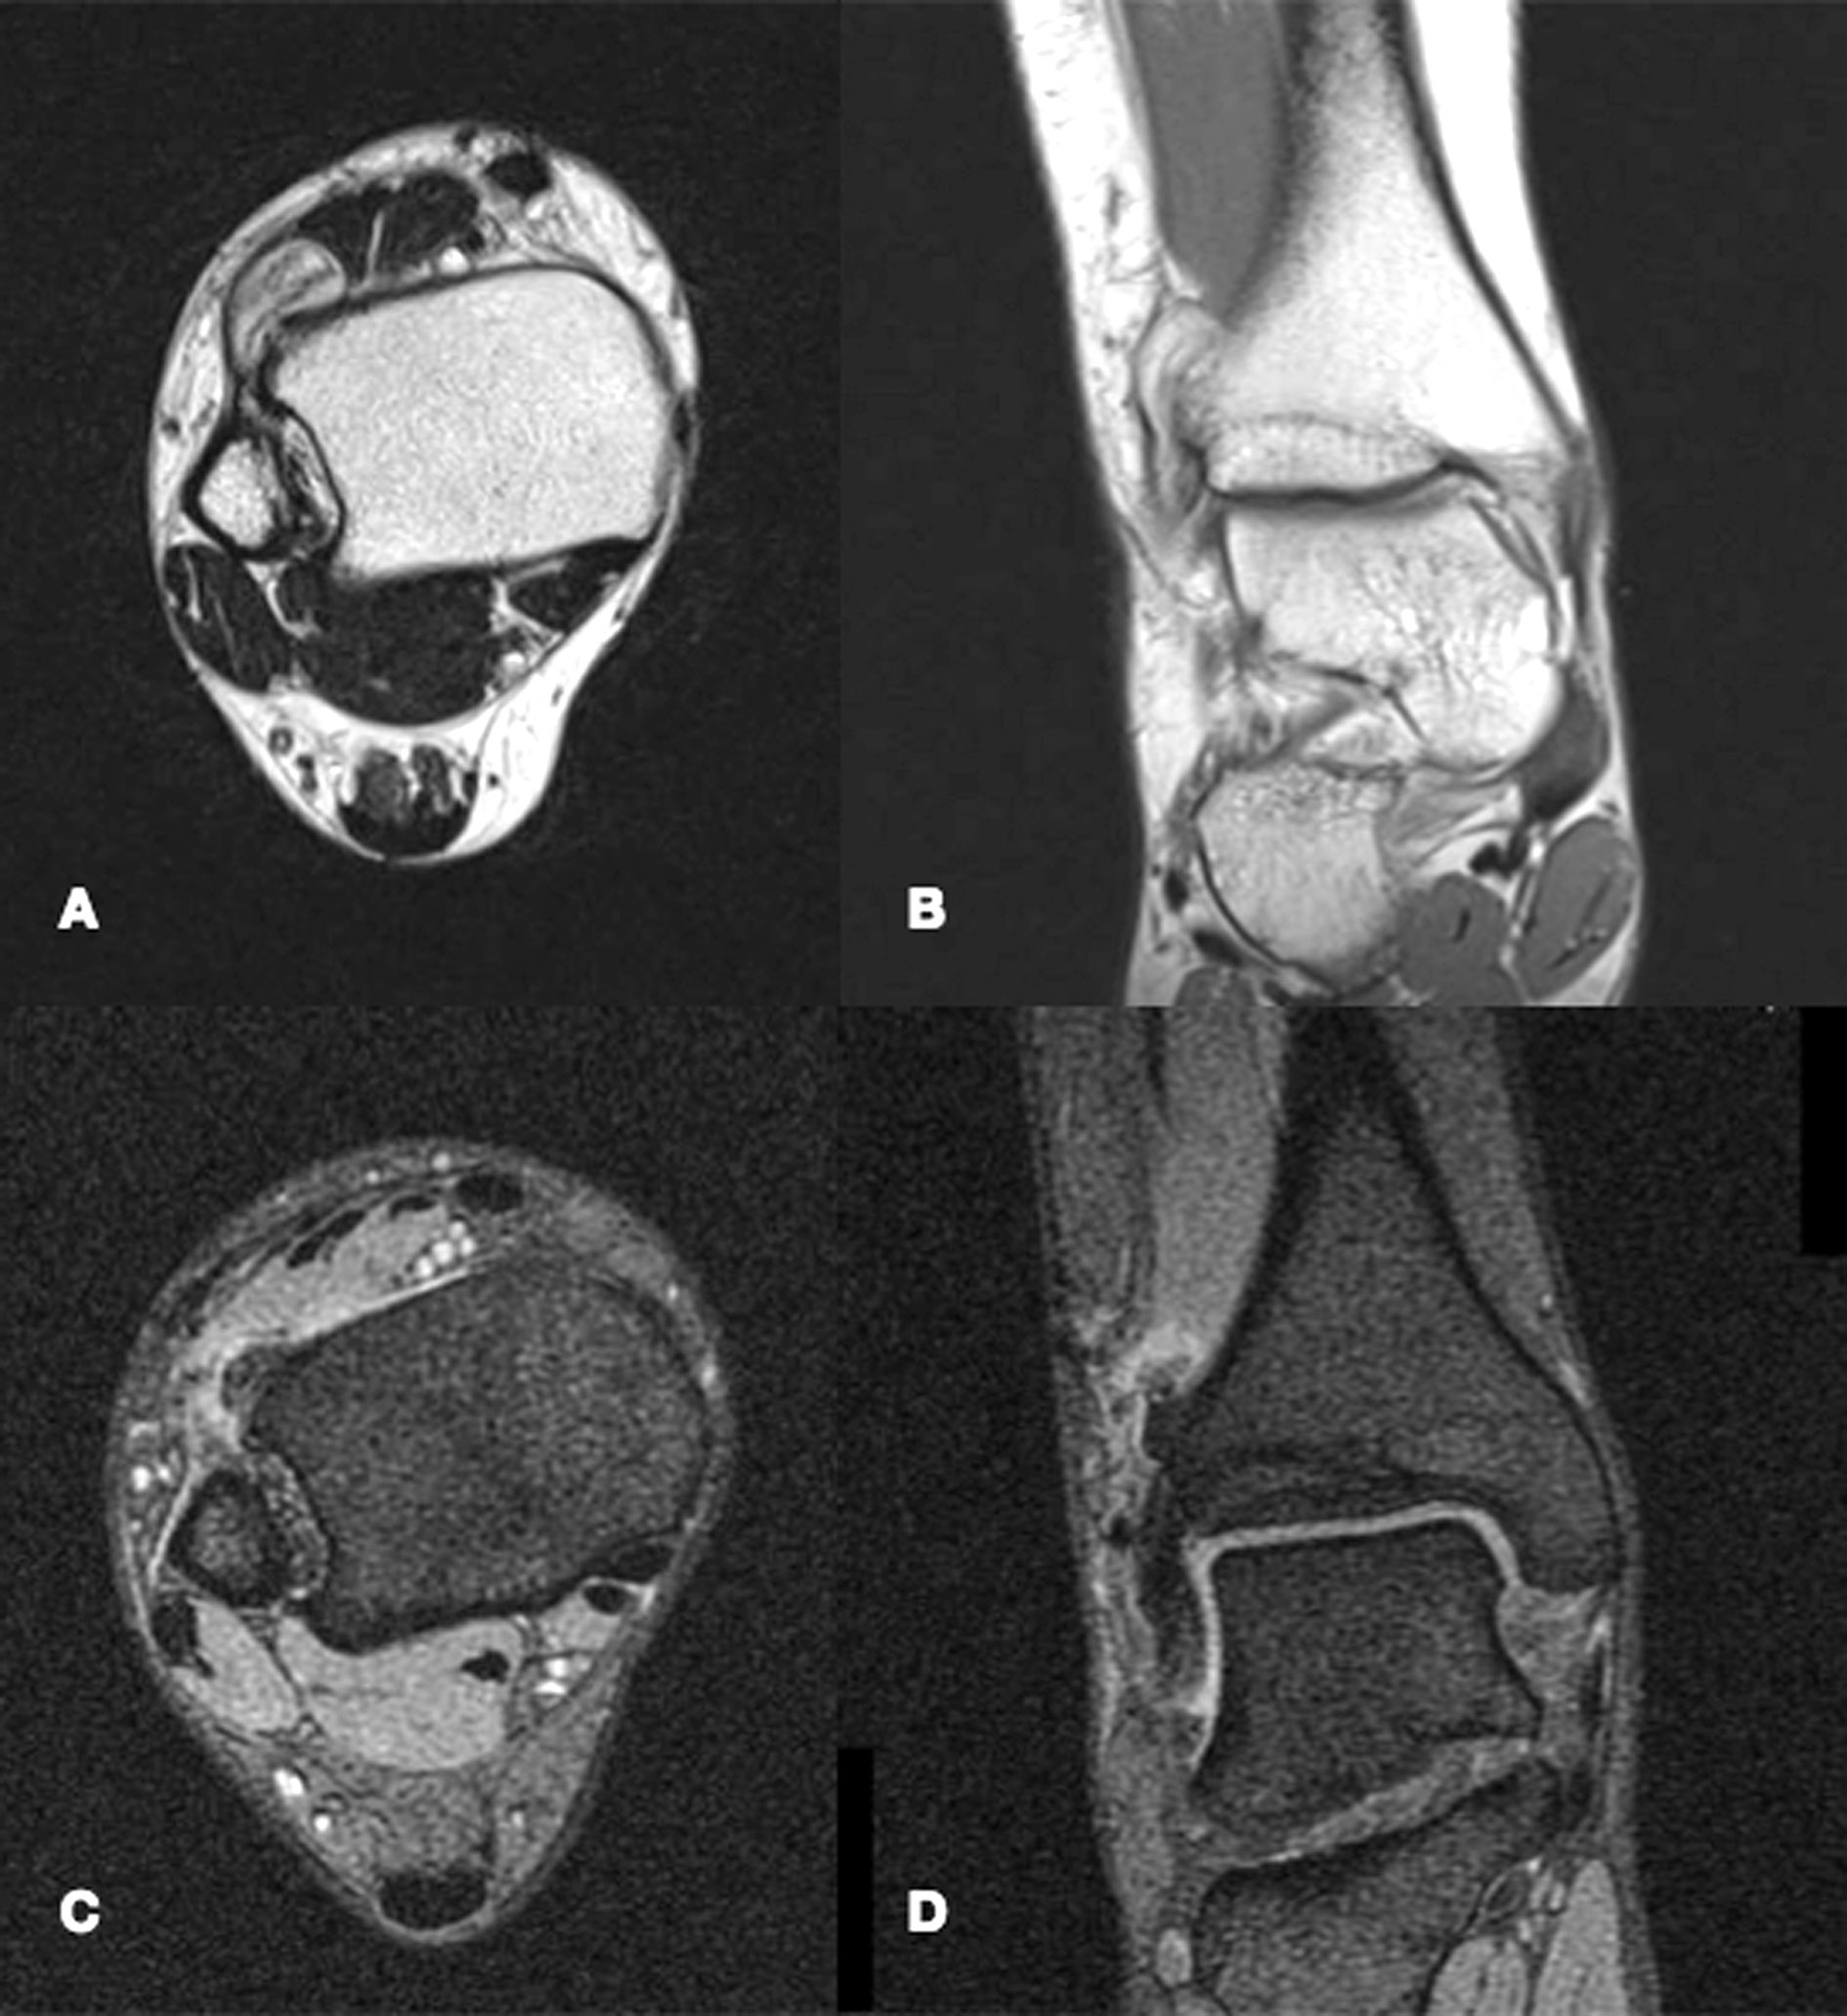

MRI – Magnetic resonance displays a Nora lesion with homogeneous low-signal intensity in T1 weighted sequences. In T2 weighted and STIR sequences, instead, the mass shows a slightly increased signal intensity in its center, with its periphery being of higher signal intensity. On T2 weighted gradient imaging, the central portion of the lesion was of inhomogeneous intermediate signal with a uniformly high signal periphery [19, 23]. Signs of periosteal reaction or perilesional oedema are exceptionally rare, although occasionally described in literature [5], and their recognition should orient physicians towards a different diagnosis (Fig. 4).